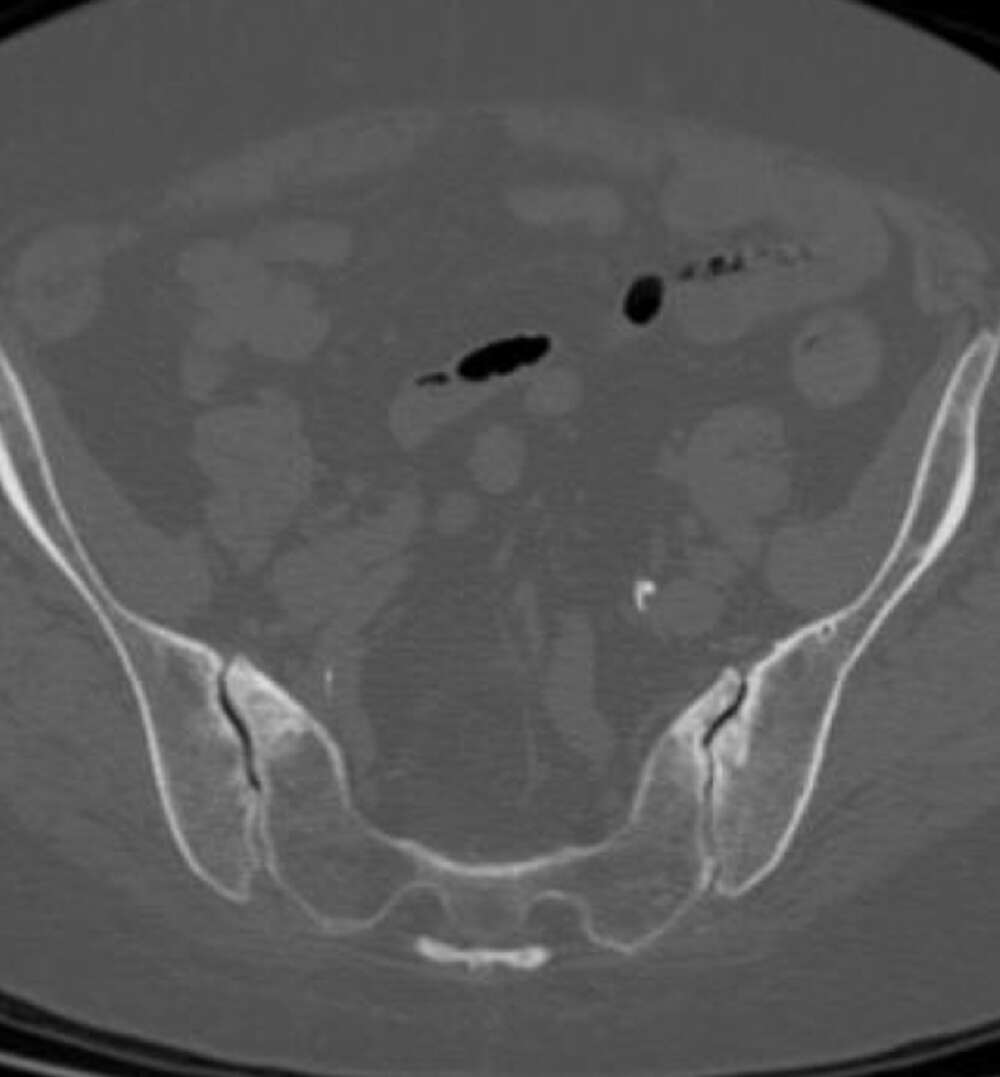

- CT of lumbar spine at +2 years post-op shows confirmation of the SI joint fusion.